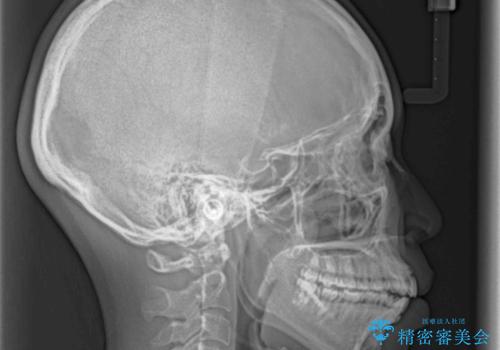

気がつくと唇が開く 口元を下げる抜歯矯正

- 口が閉じにくさを気にして来院された患者様です。

上下の前歯が前方に突出していたため、上下左右の第一小臼歯4本を抜歯し、ワイヤー装置にて抜歯矯正を行うこととしました。

上下前歯部の被蓋関係を改善するの時間がかかり、3年間を要することとなりましたが、スッキリとした口元に仕上がりました。